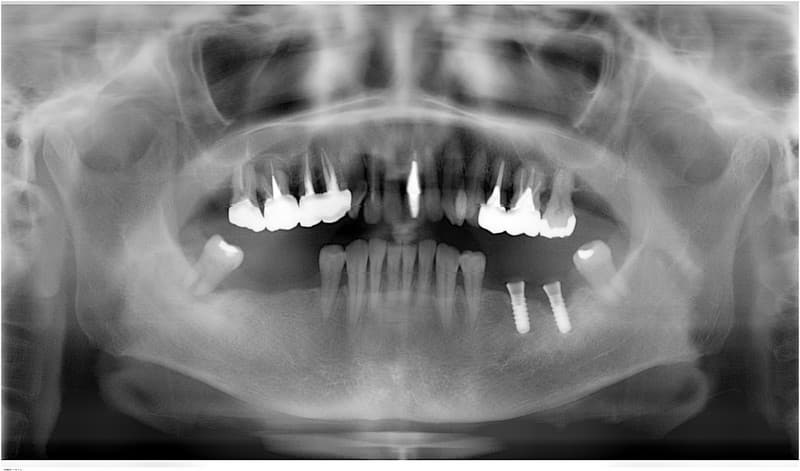

病歴や健康状態に関する問診、口の中の検査、レントゲン写真や歯型の採取

- 外科処置によって顎の骨にインプラントを埋め込みます。

- 3~6ヶ月後にインプラントに人工の歯を連結するためのパーツを取り付けます。

(小外科処置を伴います。)